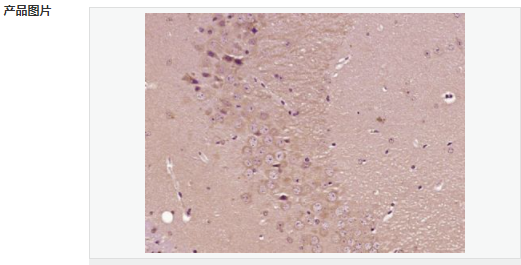

| 产品应用 | ELISA=1:5000-10000 IHC-P=1:100-500 IHC-F=1:100-500 IF=1:100-500 (石蜡切片需做抗原修复) not yet tested in other applications. optimal dilutions/concentrations should be determined by the end user. |

| 细胞定位 | 细胞浆 |